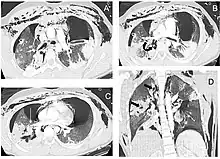

![]() | |

| Reconstruction of the trachea and bronchi with x-ray computed tomography showing disruption of the right main bronchus with abnormal lucency (arrow)[1] | |